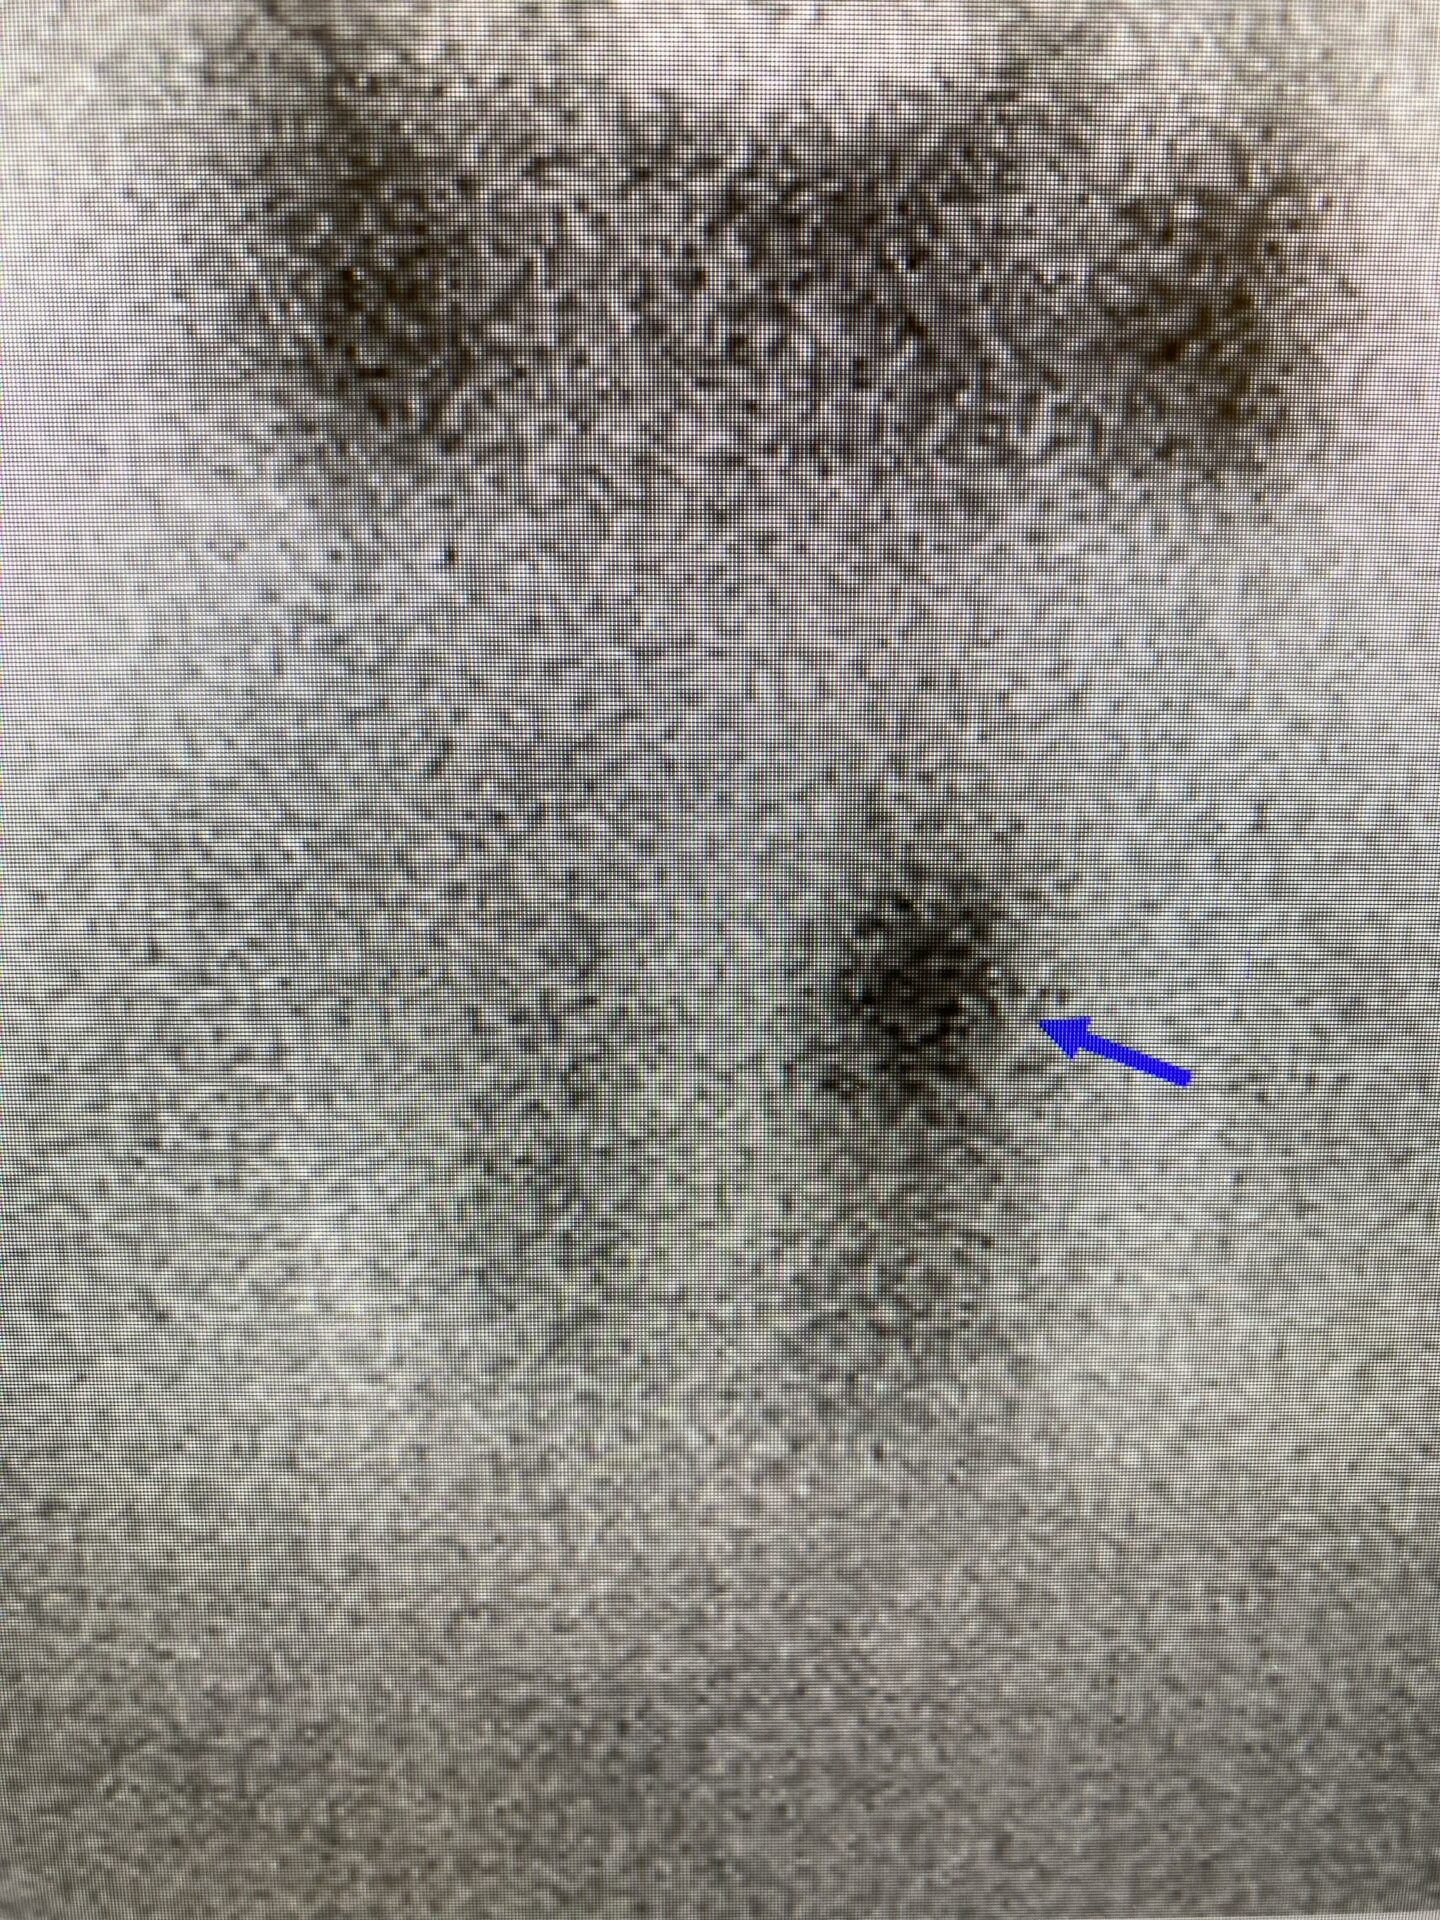

原発性副甲状腺機能亢進症疑いにて、近隣施設へご紹介したところ、副甲状腺シンチグラフィーで4腺ある副甲状腺のうち、左上腺に集積が認められておりました。

この方はもともと検診でも腎結石を指摘されており、また、多発性に尿路結石を認めていたため、Ca、P含め採血施行したところ、Ca10.6mg/ml(8.4-10.4)、p2.2mg/ml(2.5-4.5)と軽度の高Ca血症と低P血症を認めていました。そこで、intact-PTHを測定したところ、132pg/ml(10-65)と有意に上昇していたため、近隣施設へご紹介したところ、副甲状腺シンチグラフィーで副甲状腺左下腺に集積が認められたため、後日摘除し、病理学的にも腺腫の診断であったとのことでした。